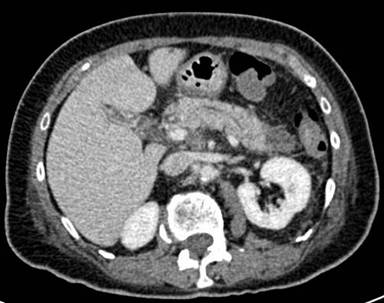

A 72-year-old female presented with acute epigastric pain radiating to her back, associated with nausea and vomiting. There was no associated hematemesis, jaundice or fever. The following illnesses were of note in her medical history: a cholecystectomy (for biliary colic attacks), hypertension and osteoarthritis. She was taking 100 mg/day of atenolol and 2 g/day of paracetamol. She abstained from all alcohol consumption. On examination, she appeared to be in pain and was dehydrated. Her abdomen was supple with epigastric tenderness. Laboratory examination revealed leukocytosis (11,500 mm-3; reference range: 4,000-10,000 mm-3). Pancreatic enzymes were abnormally increased (lipase: 956 IU/L, reference range: 114-286 IU/L; amylase: 765 IU/L, reference range: 25-115 IU/L). Hepatic enzymes, calcemia and triglyceridemia were all within the normal range and there was no biological cholestasis. An abdominal CT-scan confirmed the diagnosis of acute pancreatitis (Balthazar computed tomography grading system C) and revealed a ring of inflammatory tissue surrounding the second duodenum which was isodense with pancreatic tissue, leading to the diagnosis of annular pancreas (Figures 1 and 2). The biliary ducts were not dilated and no residual stones were seen in the bile ducts at MR cholangiography and endoscopic ultrasound. Double-contrast barium radiography showed stenosis of the second duodenum associated with proximal dilation of the duodenal bulb and stomach, classically known as the “double bubble” sign (Figure 3). An endoscopic biopsy of the stenotic portion of the duodenum was performed and did not reveal any tumoral tissue. In view of these findings, the diagnosis of acute pancreatitis secondary to annular pancreas was confirmed. The duodenal occlusion was related to the stenosis of the second duodenum caused by the pancreatitis. Medical treatment based on her symptoms was then begun. The treatment progressively reduced the pain and no complications occurred. After three weeks of nasojejunal liquid feeding, the patient was again able to eat solid food and she was then discharged. In light of the patient’s age, and the fact that it was her first clinical manifestation of acute pancreatitis related to annular pancreas, a Whipple’s procedure was not indicated.

Figure 2. Abdominal CT scan: body of the pancreas without major involvement of pancreatitis. |